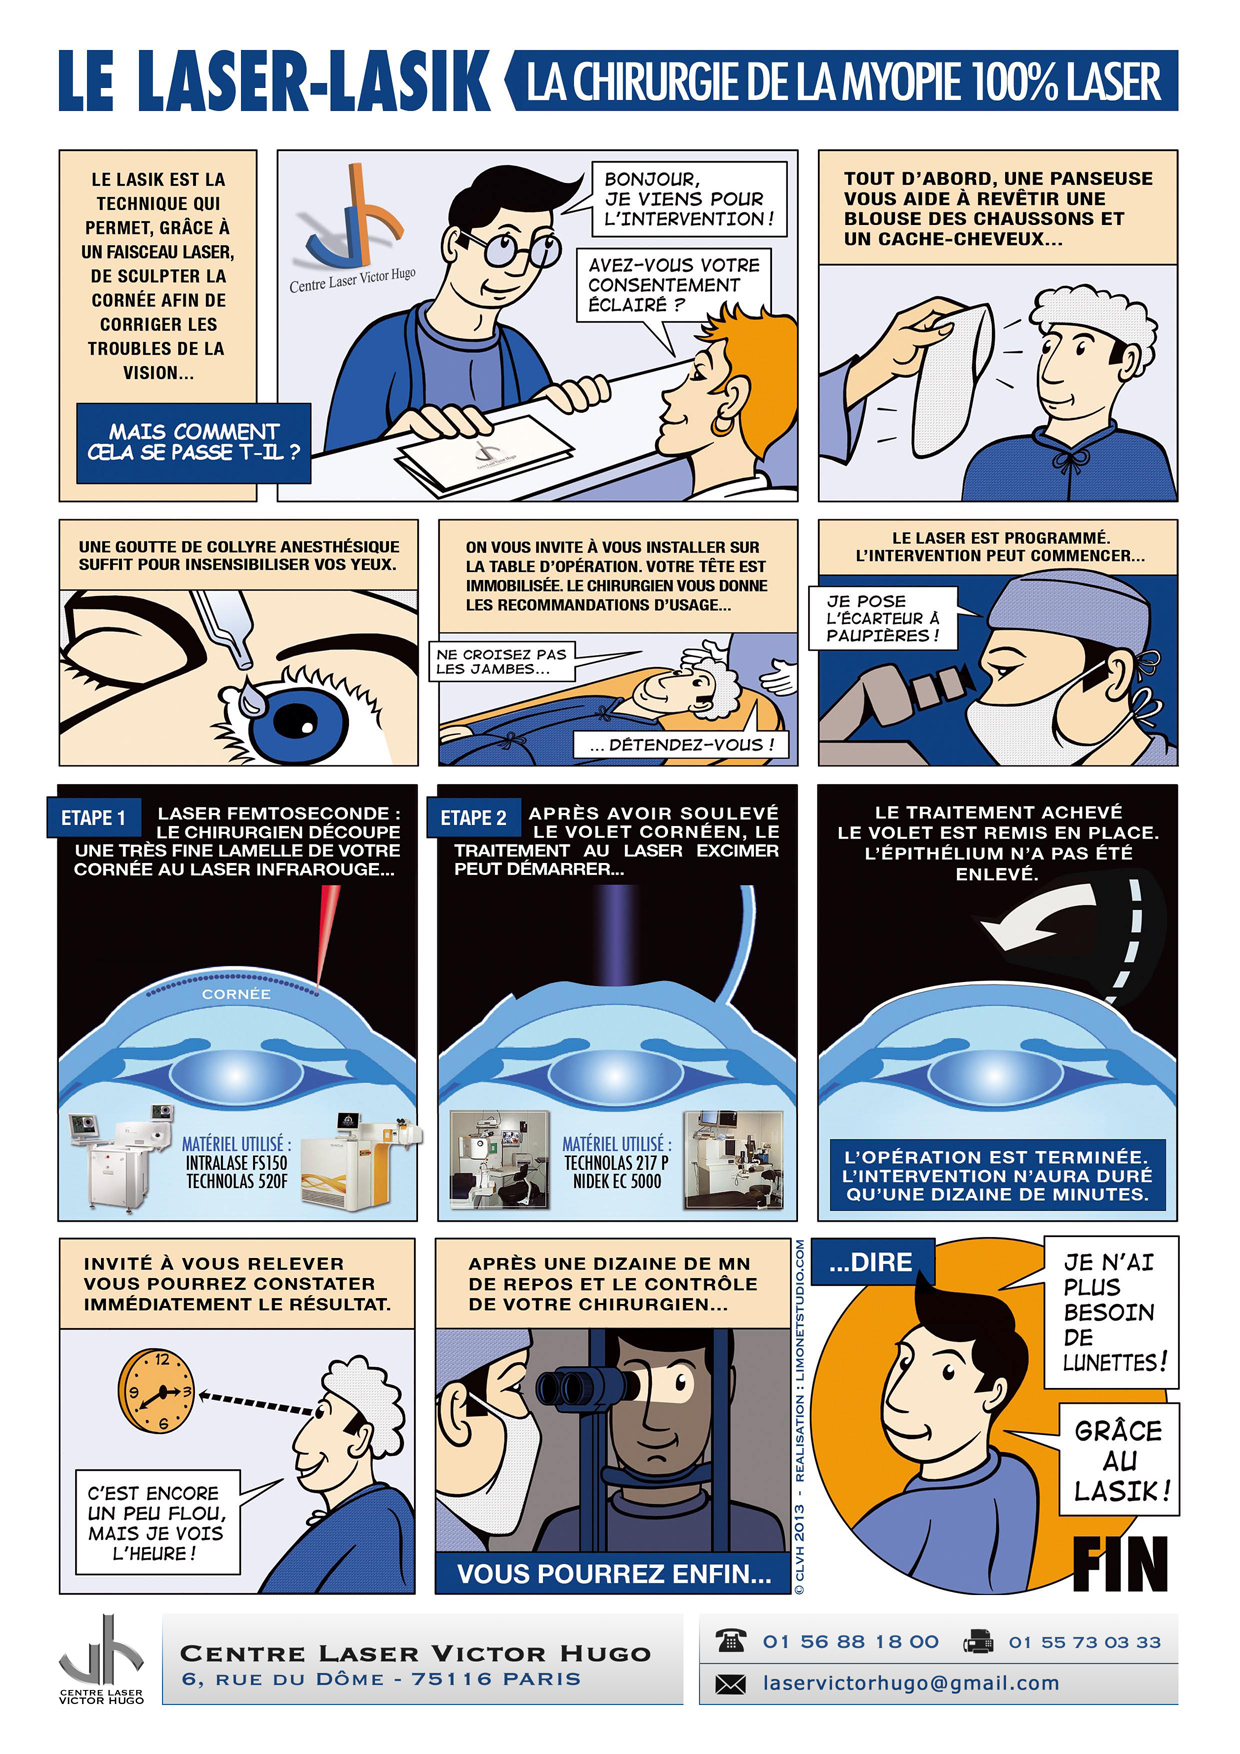

Afin de répondre aux interrogations d'un public de plus en plus intéressé, nous vous proposons cet ouvrage explicatif sous la forme d'une bande dessinée ludique. Cette bédé aborde les troubles de la vision, la chirurgie réfractive (LASIK, PKR et PresbyLASIK), la technique des anneaux et des implants. Cette bébé aborde également l'amblyopie et son traitement orthoptique. Maintenant... à vous de voir !